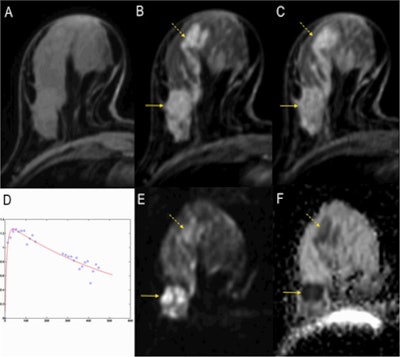

Breast MRI is also progressing. Unenhanced MRI may simplify the approach to breast MRI by omitting costs, time effort, and potential side effects related to contrast agents, including circulation-related effects, allergies, nephrogenic systemic fibrosis, according to Dr. Pascal Baltzer, associate professor in the radiology department at the Medical University of Vienna. An imaging protocol using unenhanced MRI only -- as in diffusion-weighted imaging (DWI) together with T2-weighted anatomical images -- would require about five to 10 minutes of magnet time, thus allowing the examination of at least six patients per hour, he said. Also, reduced costs could broaden the availability of breast MRI.

![A full examination at 3 tesla. A, B, and C: Precontrast T1-weighted imaging, early and delayed postcontrast scans depicting a mass (invasive ductal carcinoma, arrow) and associated clapped segmental nonmass enhancement (dashed arrow, ductal carcinoma in situ [DCIS]). D: The SI-time curve of the mass, indicating a malignant lesion by washout type 3 curve. E: The DWI image where the cancer lesions can be seen hyperintense similar to contrast-enhanced images. F: The apparent diffusion coeficient (ADC) map where the tumors are indicated by low signal intensity corresponding to typical restricted diffusion. Note that the signal of the invasive cancer is lower than that of the DCIS, confirming the ability of DWI to demonstrate quantitative differences in tissue microstructure not only able to diagnose cancer but also to differentiate invasive from noninvasive cancer. Images courtesy of Dr. Pascal Baltzer.](https://img.auntminnieeurope.com/files/base/smg/all/image/2015/03/ame.2015_03_04_22_11_00_218_2015_03_05_enhanced_MRI1.png?auto=format%2Ccompress&fit=max&q=70&w=400)

"The issue is the broad variability of DWI imaging results," he noted. "Although several initial studies have demonstrated a similar performance of unenhanced breast MRI compared with breast MRI, these studies did not answer how good unenhanced MRI is for specific indications (such as high-risk screening, etc.). Furthermore, potential pitfalls such as mastopathic changes, small and nonmass lesions have not been closely investigated."

At the moment, contrast-enhanced breast MRI is the standard of care, and this won't change until more research has covered the field of unenhanced breast MRI. "However, we have to keep in mind that leading experts in prostate MRI openly discuss whether contrast agent application is really necessary," he said.

Unenhanced breast MRI could be used in nearly all fields of breast MRI, given an appropriate DWI technique, he remarked. However, typical pitfalls include chronic inflammatory conditions such as regularly seen in postsurgical conditions.